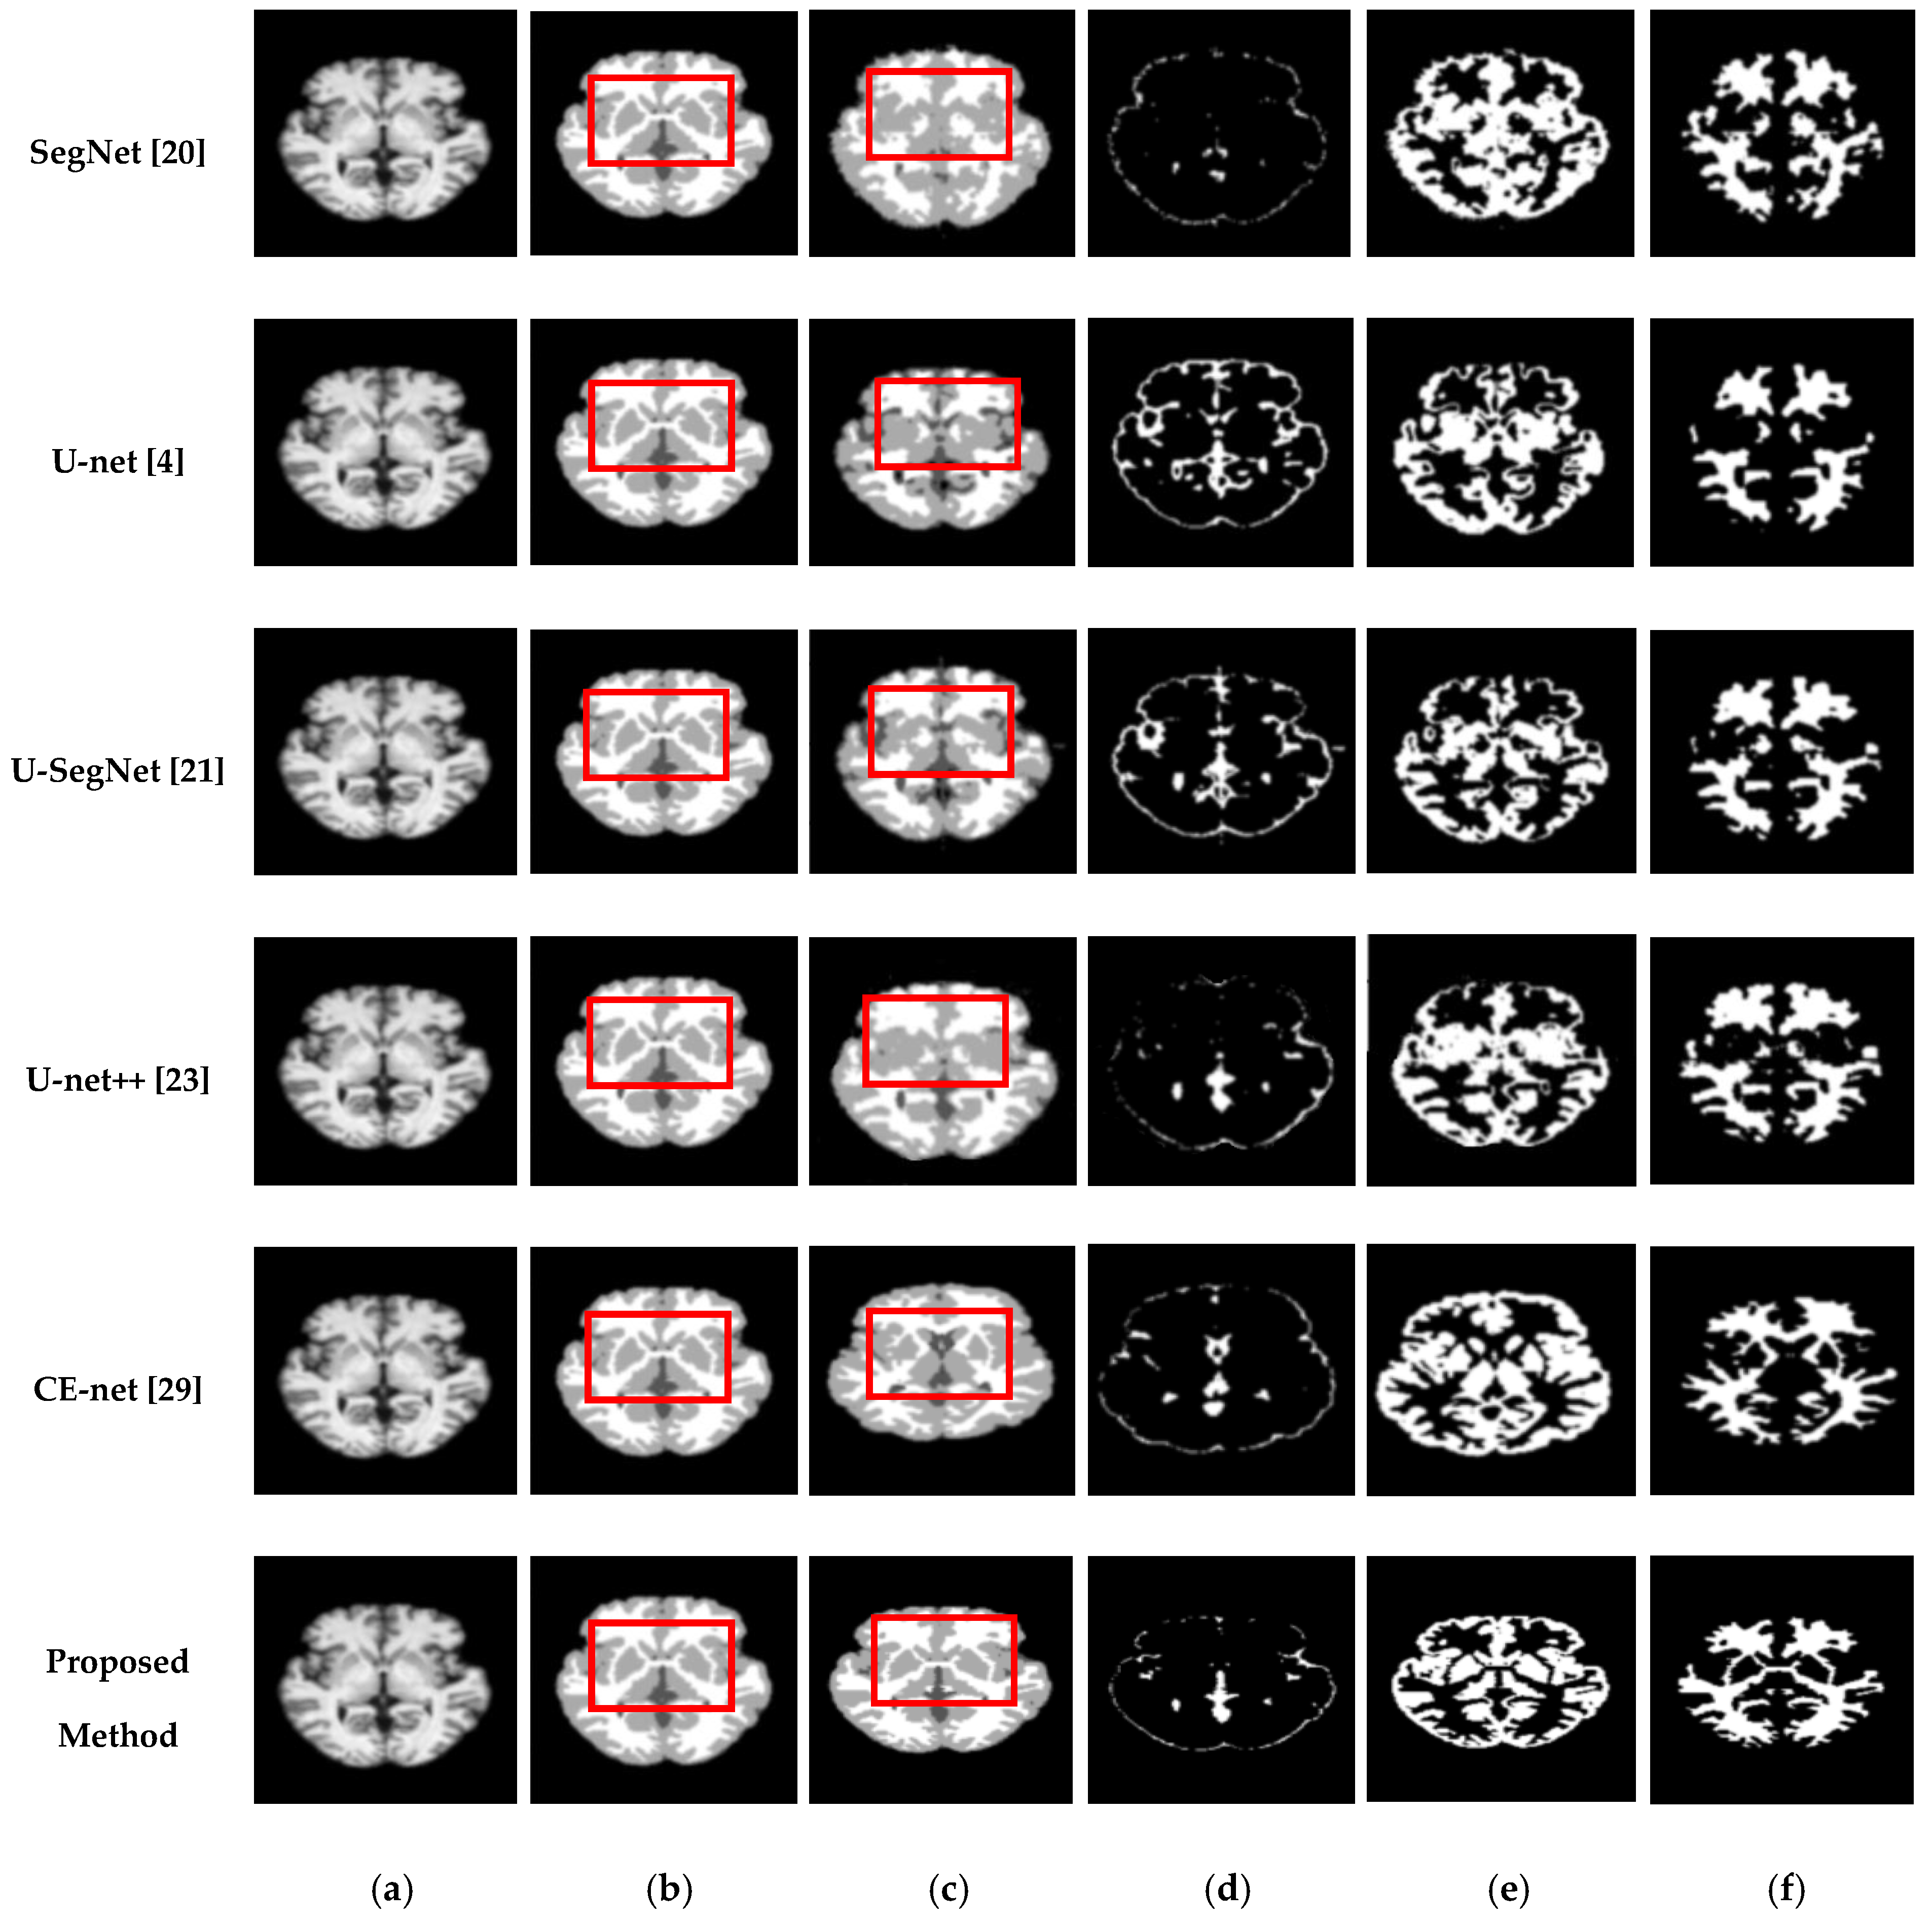

We also assessed the segmentation performance in terms of the mean square error (MSE), which is the average square difference between the original and predicted Y values. The Hausdorff distance (HD) [] was used to determine the dissimilarity between two sets in a metric space. The two sets of small Hausdorff distances are almost identical. HD and MSE are computed as listed in Table 2, where D is the Euclidean distance between two pixels, and R and C are the image height and width, respectively. To compare the segmentation results of various network architectures, we experimented on SegNet, U-net, U-SegNet, U-net++, and CE-net models under the same experimental conditions. Figure 7 and Figure 8 show comparisons of the segmentation results. As shown in Figure 7 and Figure 8, the proposed method shows superior results in terms of the quality of the segmentation map compared to those of other conventional methods. Although the skip connections in the U-net improve feature representations by combining low-level and high-level information, they suffer from a large semantic gap between low- and high-resolution feature maps, resulting in high misclassification rates of brain tissues. Furthermore, for medical images with low contrast, blurred boundaries between different tissues, the segmentation accuracies of U-net and SegNet are significantly degraded. Because the network layers in U-net++ are connected through a series of nested, dense skip pathways, leading to redundant learning of features, they did not show good performance. In particular, it can be observed that there are misclassification results in the feature maps generated by SegNet, U-net, and U-net++ in the red boxes of Figure 7c and Figure 8c. Although U-SegNet with pooling indices and skip connections yields better segmentation results, it fails to capture fine details, as shown in Figure 8c. From the highlighted red boxes in Figure 8, it can be observed that U-SegNet fails to identify differences between WM and GM tissues, and most of the GM tissues are incorrectly predicted as WM. The CE-net extracts multi-scale information through a context encoder block for the segmentation of medical images. However, the context encoder block is employed only at the bottleneck layer of the model, and thus this multi-scale information could be irrelevant by the time it reaches the final decoder layer for classification. To overcome these limitations, we extract multi-scale information at each network layer followed by the GAM to enhance the segmentation performance by directing attention to related areas. This improved segmentation can be observed in the results obtained using the proposed method. Similar results were observed for the segmentations obtained from the IBSR images, as shown in Figure 8. It can be observed that the proposed network obtains finer details than the other architectures. These results indicate that our proposed approach can strongly recover finer segmentation details while bypassing distractions between tissue boundary regions.

Figure 7.

Segmentation results for GM, CSF, and WM from brain MRI image using the existing methods and the proposed method on OASIS dataset: (a) original input image; (b) ground-truth segmentation map; (c) their segmentation results obtained SegNet, U-net, U-SegNet, U-net++,CE-net, and the proposed method (top to bottom); (d) CSF maps obtained by SegNet, U-net, U-SegNet, U-net++,CE-net, and the proposed method (top to bottom); (e) GM maps obtained by SegNet, U-net, U-SegNet, U-net++,CE-net, and the proposed method (top to bottom); (f) WM maps obtained by SegNet, U-net, U-SegNet, U-net++,CE-net, and the proposed method (top to bottom).